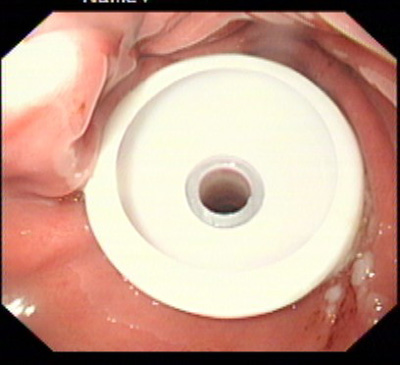

在消化科董蕾主任关心和指导下,消化科王进海教授,张利医师成功地给一位脑出血后吞咽困难的患者实施了经皮内镜下胃造瘘术。

该患者系男性,76岁,脑出血后留有吞咽困难后遗症,不能自主进食,需长期留置胃管供给营养,严重的影响了病人的生活质量和原发病的恢复。经皮内镜下胃造瘘术(Percutaneous endoscpic gastrostomy,PEG)是一种无需常规外科手术和全身麻醉的造瘘技术,可以在胃镜室或病房局麻下进行,因此是一种操作简便、创伤小、安全可靠的方法。该例患者在胃镜室局麻下进行手术,手术过程约10分钟,术后病人无明显不适,3天后即可从造瘘管给食物并出院。

该手术的成功填补了院内空白,丰富了内镜下治疗的内容。对于各种原因造成的长期或较长期不能(一月以上)经口进食者,可通过造瘘管供给病人足够的营养物质,效果优于传统的鼻胃管饲营养,费用又明显低于静脉内营养,是一项值得推广的内镜下较为安全的治疗技术。经皮内镜下胃造瘘术适应证包括:①中枢神经系统或全身性疾病导致的吞咽困难或不能吞咽。如:脑干炎症、变性,脑血管意外,脑肿瘤, 脑外伤;急性呼吸衰竭;系统性硬化症、重症肌无力;完全不能进食的神经性厌食或神经性呕吐导致严重的营养不良,而不能耐受手术造瘘者;②口、咽、喉手术前后及头颈部肿瘤放疗期间,需较长时间营养支持者。③食管广泛瘢痕者;④严重的胆外瘘需将胆汁引回胃肠道者;⑤各种原因所致呼吸功能障碍须气管切开,同时需PEG者;⑥胃肠减压(一月以上的鼻胃管留置者)的目的。